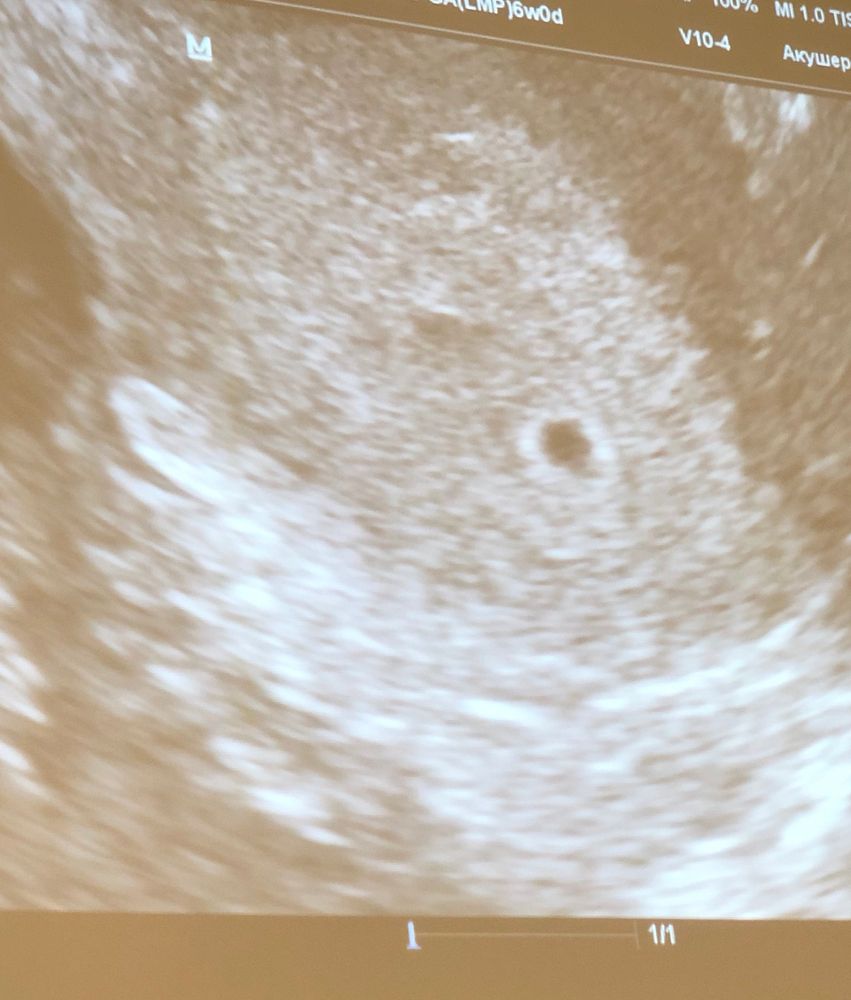

первое УЗИ🥰

Беременность- 1 триместр ( только до 10 недель)Девочки привет! Ну теперь немного отлегло! Подтвердили беременность, бусинка моя в матке 🙏🏻 Теперь по меньше читать всякой инфы про возможные исходы, только положительные эмоции и ожидание 2 недели до УЗИ, чтобы посмотреть на эмбриончик🥰 Завтра буду сообщать мужу, а то сил уже нет целую неделю в себе держать этот секрет😁 да и к тому же надо как то объяснить ему половой покой😁 (врач сказала, что ЖТ переросло в кисту и поэтому меня беспокоит правый Я, и нужно исключить пока физ нагрузки и соблюдать половой покой)❤️Вот такие вот дела 🥰